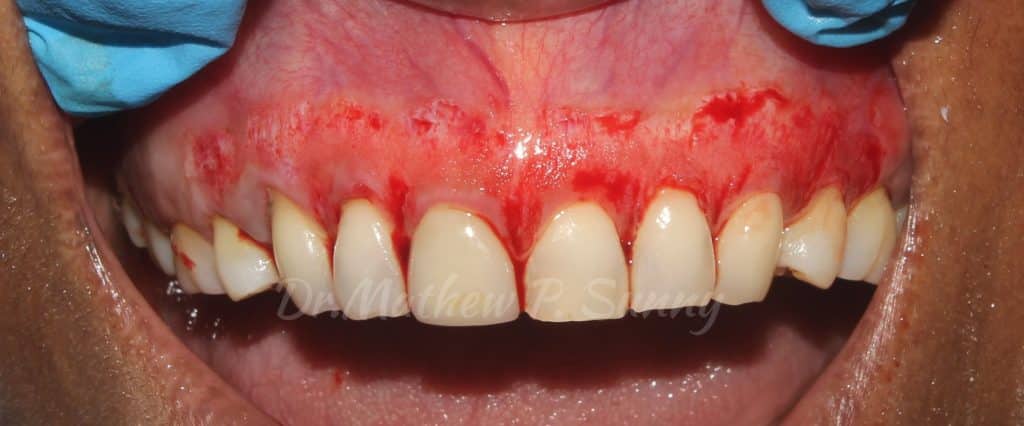

The present case demonstrates the use of diamond burs used on a high speed handpiece to carefully remove the superficial layer of epithelium to expose the underlying connective tissue..

The denunded connective tissue then heals by secondary intention. Bleeding during the procedure is controlled by using gauze soaked in local anaesthetic solution with 1:80000 Adrenaline concentration.

Intra Oral presentation..showing the clear extent of the pigmentation of the marginal attached tissues..

A course diamond bur is used to abrade the tissues carefully. Here a high speed handpiece was used. One can also consider the use of a low speed handpiece for greater control during the procedure..

after initial analyses, some areas of pigmentation was noted to have been missed, these areas were further abraded..